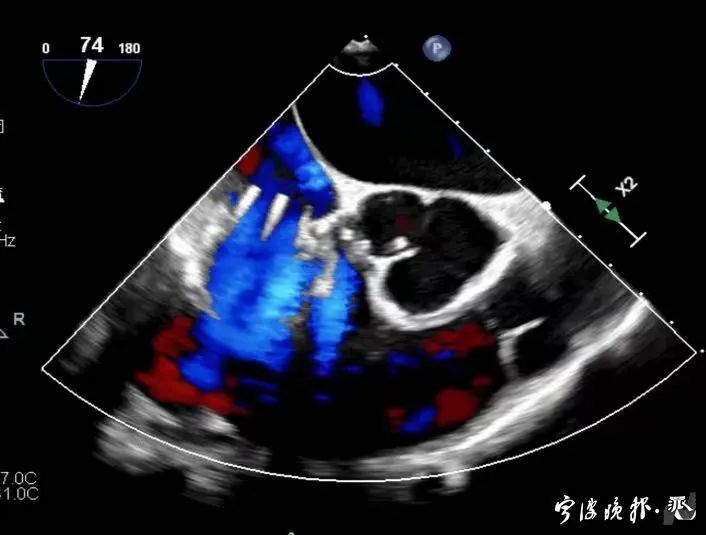

術(shù)前食道心超示三尖瓣重度反流

術(shù)后食道心超示三尖瓣反流消失